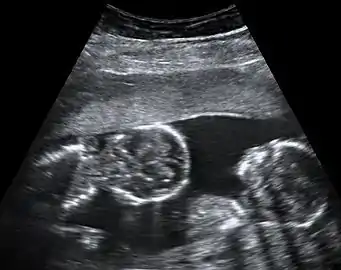

Ultrasound is the only way to detect monoamniotic-monochorionic twins before birth.[4] It can show the lack of a membrane between the twins after a couple of weeks' gestation, when the membrane would be visible if present.[4]

Further ultrasounds with high resolution doppler imaging and non-stress tests help to assess the situation and identify potential cord problems.[4]